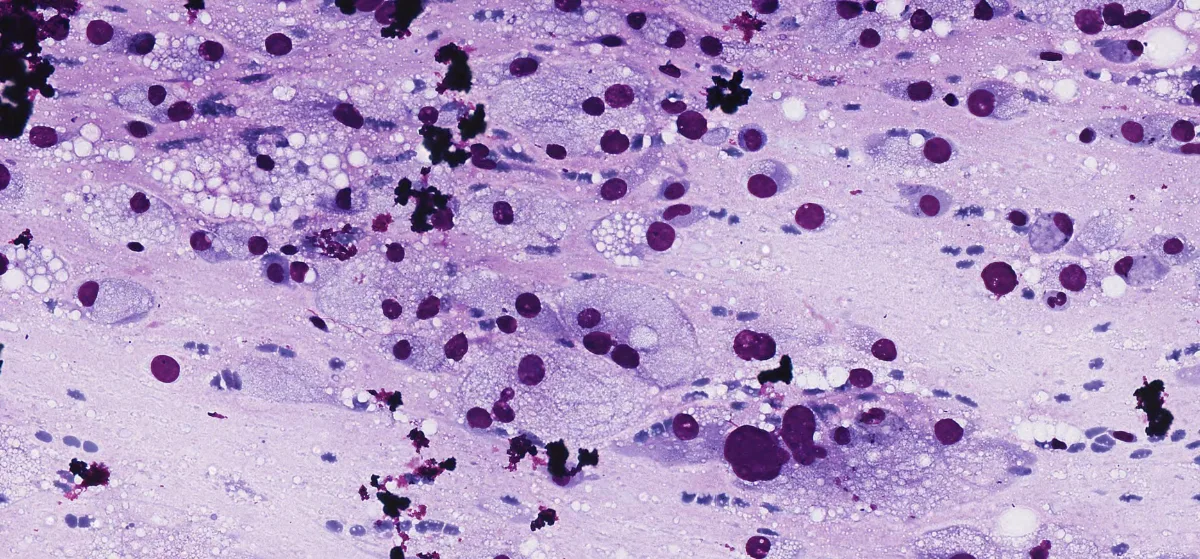

Paciente femenina de 15 años sin antecedentes. Presenta una masa en región cigomática derecha de 3 cm, firme, no dolorosa, sin signos inflamatorios, aparecida en el contexto de un tratamiento de ortodoncia. La resonancia magnética sugiere una lesión inflamatoria, pero tras tratamiento antibiótico sin mejoría, se realiza PAAF intraoral. La citología muestra células atípicas con características lipoblastoides, abundante fondo mixoide y vascularización capilar plexiforme. Se observan mitosis atípicas y positividad para Vimentina y Adipofilina. No se detectan translocaciones de DDIT3 ni PLAG1, ni amplificación de MDM2.

Diff-Quik Cito 2

Diff-Quik Cito 3